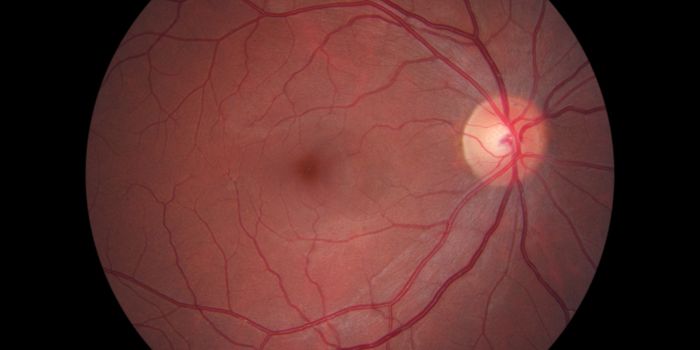

SEP 27, 2016Cell & Molecular BiologyCell Regeneration in Your Eyes Could Treat Retinal Blindness Diseases